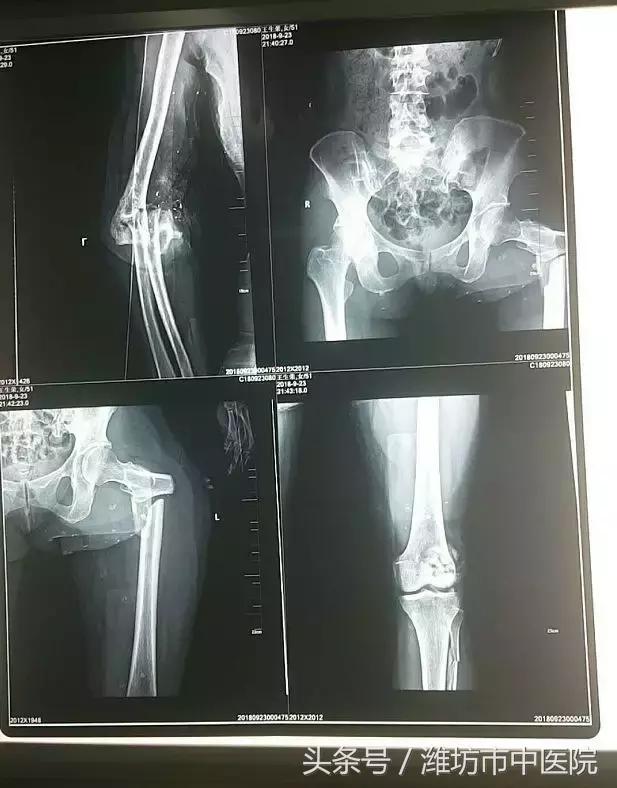

患者全身10余处骨折,面部外伤、双眼球破裂并异物滞留,失血性休克。病情危急,刻不容缓,补液,纠正循环,备血,输血,手足外科医疗团队成员先后赶到现场,讨论患者的救治方案,CT检查,排除胸腹部脏器损伤后紧急送入手术室。

患者足关节开放损伤、大面积皮肤软组织缺损、骨折脱位并骨缺损,髌骨开放性粉碎骨折并骨缺损,股骨近端粉碎性骨折,左足踝部多处骨折并脱位,患者创伤性休克,病情危急。团队经讨论决定,先对肘关节、膝关节两处开放性损伤进行手术,股骨近端、足踝部骨折二期手术的方案。

术中见髌骨粉碎严重,部分骨缺损,关节面严重压缩,左肘部开放性骨折、肘关节脱位、骨缺损伴严重污染。多根血管神经肌腱断裂,手术难度极大,为减少感染风险,避免增加手术创伤,术中给予彻底清创,仔细复位髌骨关节面及尺骨近端骨折以钛揽张力带内固定同时外固定架固定肘关节,救治医疗团队经过六小时的奋战,顺利完成了对肘关节膝关节严重开放骨折的手术。